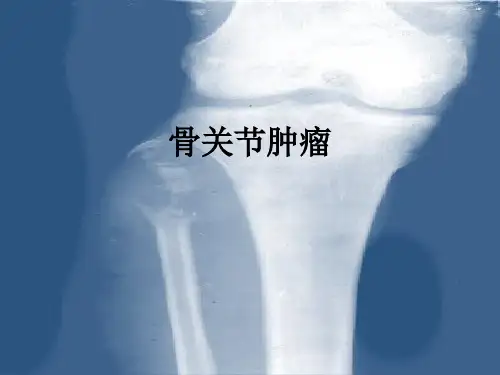

骨关节肿瘤疾病课件二-临床病理专业 医学技术PPT

骨肿瘤1.良性肿瘤*骨软骨瘤的临床表现、X线表现及治疗2.骨巨细胞瘤(1)*分级(2)*临床表现(3)*X线表现及诊断(4)*治疗原则3.原发性恶性肿瘤(1)*骨肉瘤的病理、临床及X线表现、手术治疗原则(及其进展)(2)*尤文氏瘤的病理、临床、X线表现、治疗4.转移性骨肿瘤*定义5.骨的瘤样病损*骨囊肿的临床表现及治疗一、良性肿瘤——骨软骨瘤好发年龄:青少年。

二、骨巨细胞瘤——潜在恶性或介于良恶之间的溶骨性肿瘤。